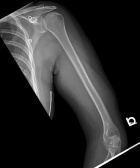

16 yo female w/ 6 mo h/o of painful mass in L arm with increasing size. Complains of dysthesias in her 4th and 5th digits. Denies constitutional symptoms. Previous bx reported as fatty tissue.

PE: Significant palpable, painful mass in posterior LUE. No erythema or overlying skin changes. Full ROM at shoulder and elbow. Decreased sensation to 4th webspace and 5th digit. 2+R/U pulses. No LAN.